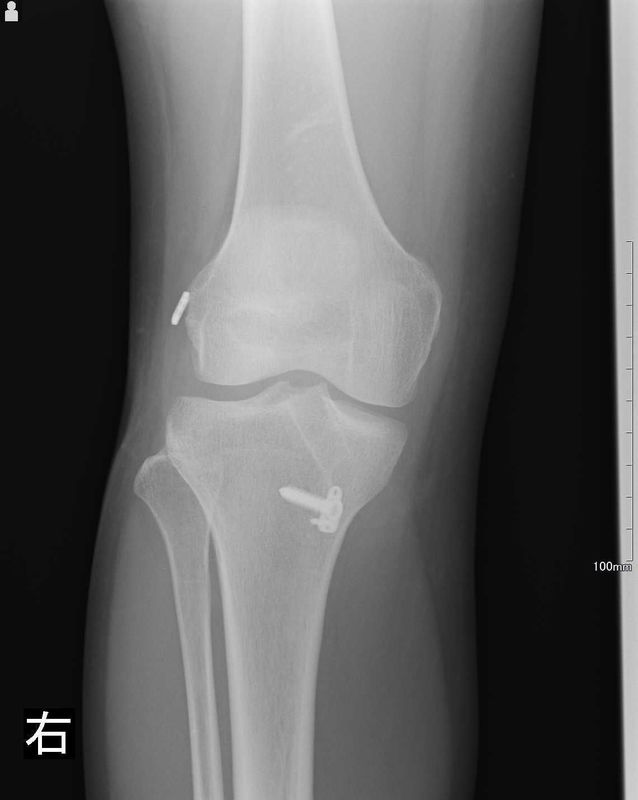

レントゲン所見

| 手術前 | 手術後 |

| 骨傷・変形はない | 異常なし |